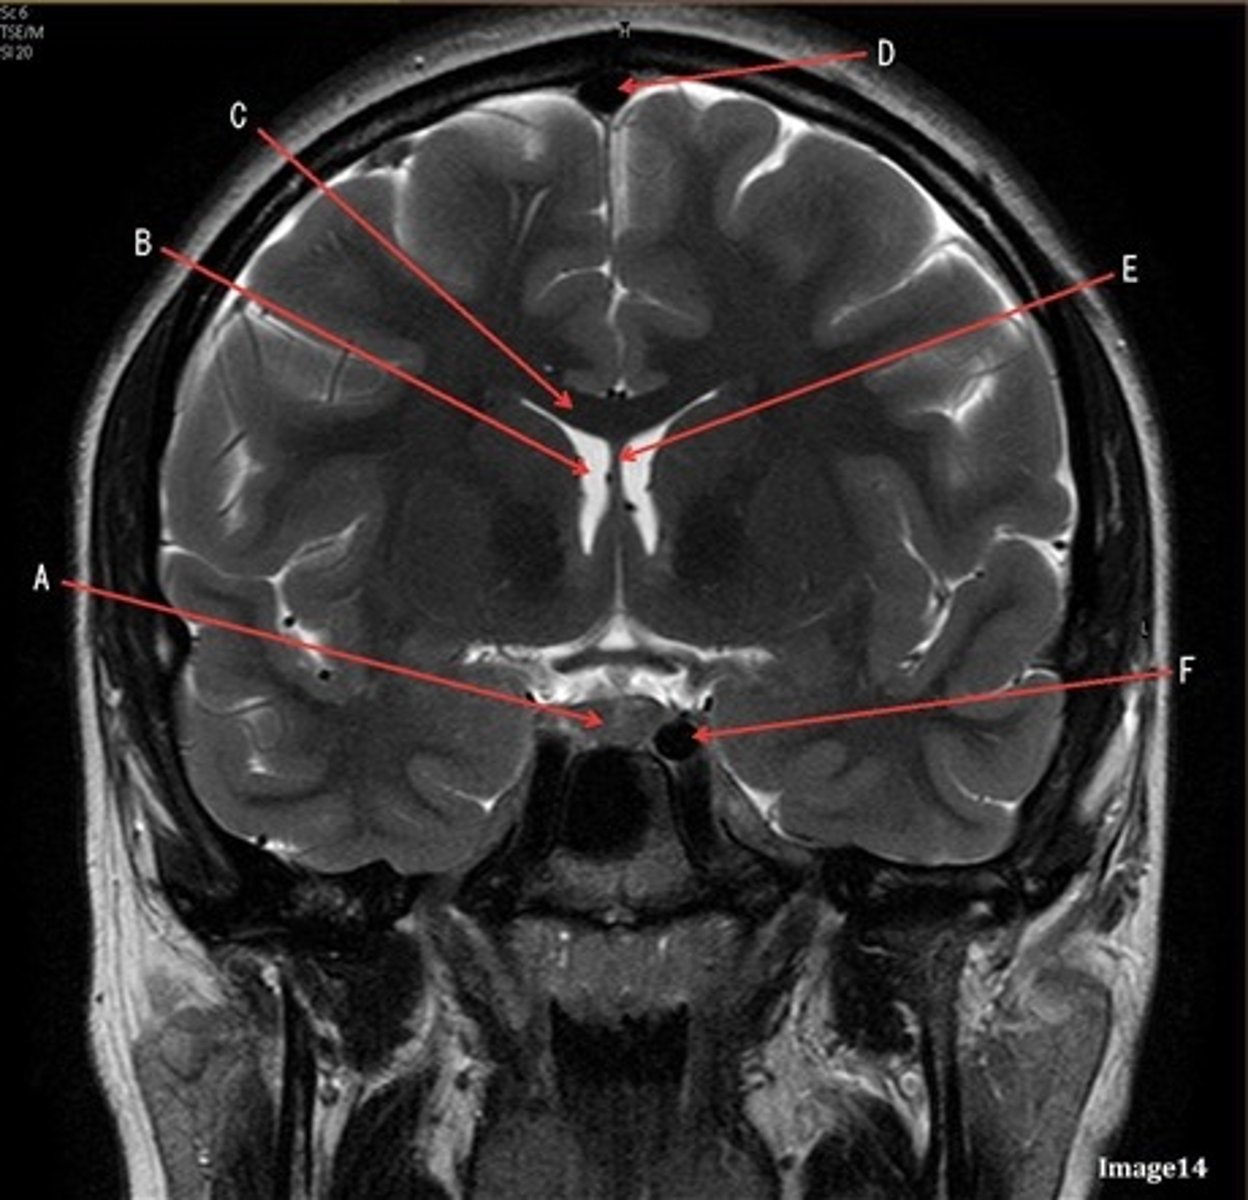

A

lateral ventricle

B

corpus callosum

C

thalamus

D- separates what

tentorium cerebelli- cerebrum (occipital and temporal lobes) from brainstem and cerebellum

E

fourth ventricle

F

medulla oblongata

caudate nucleus

third ventricle

D

lentiform nucleus

frontal sinus

pituitary gland

corpus

fornix

internal carotid artery